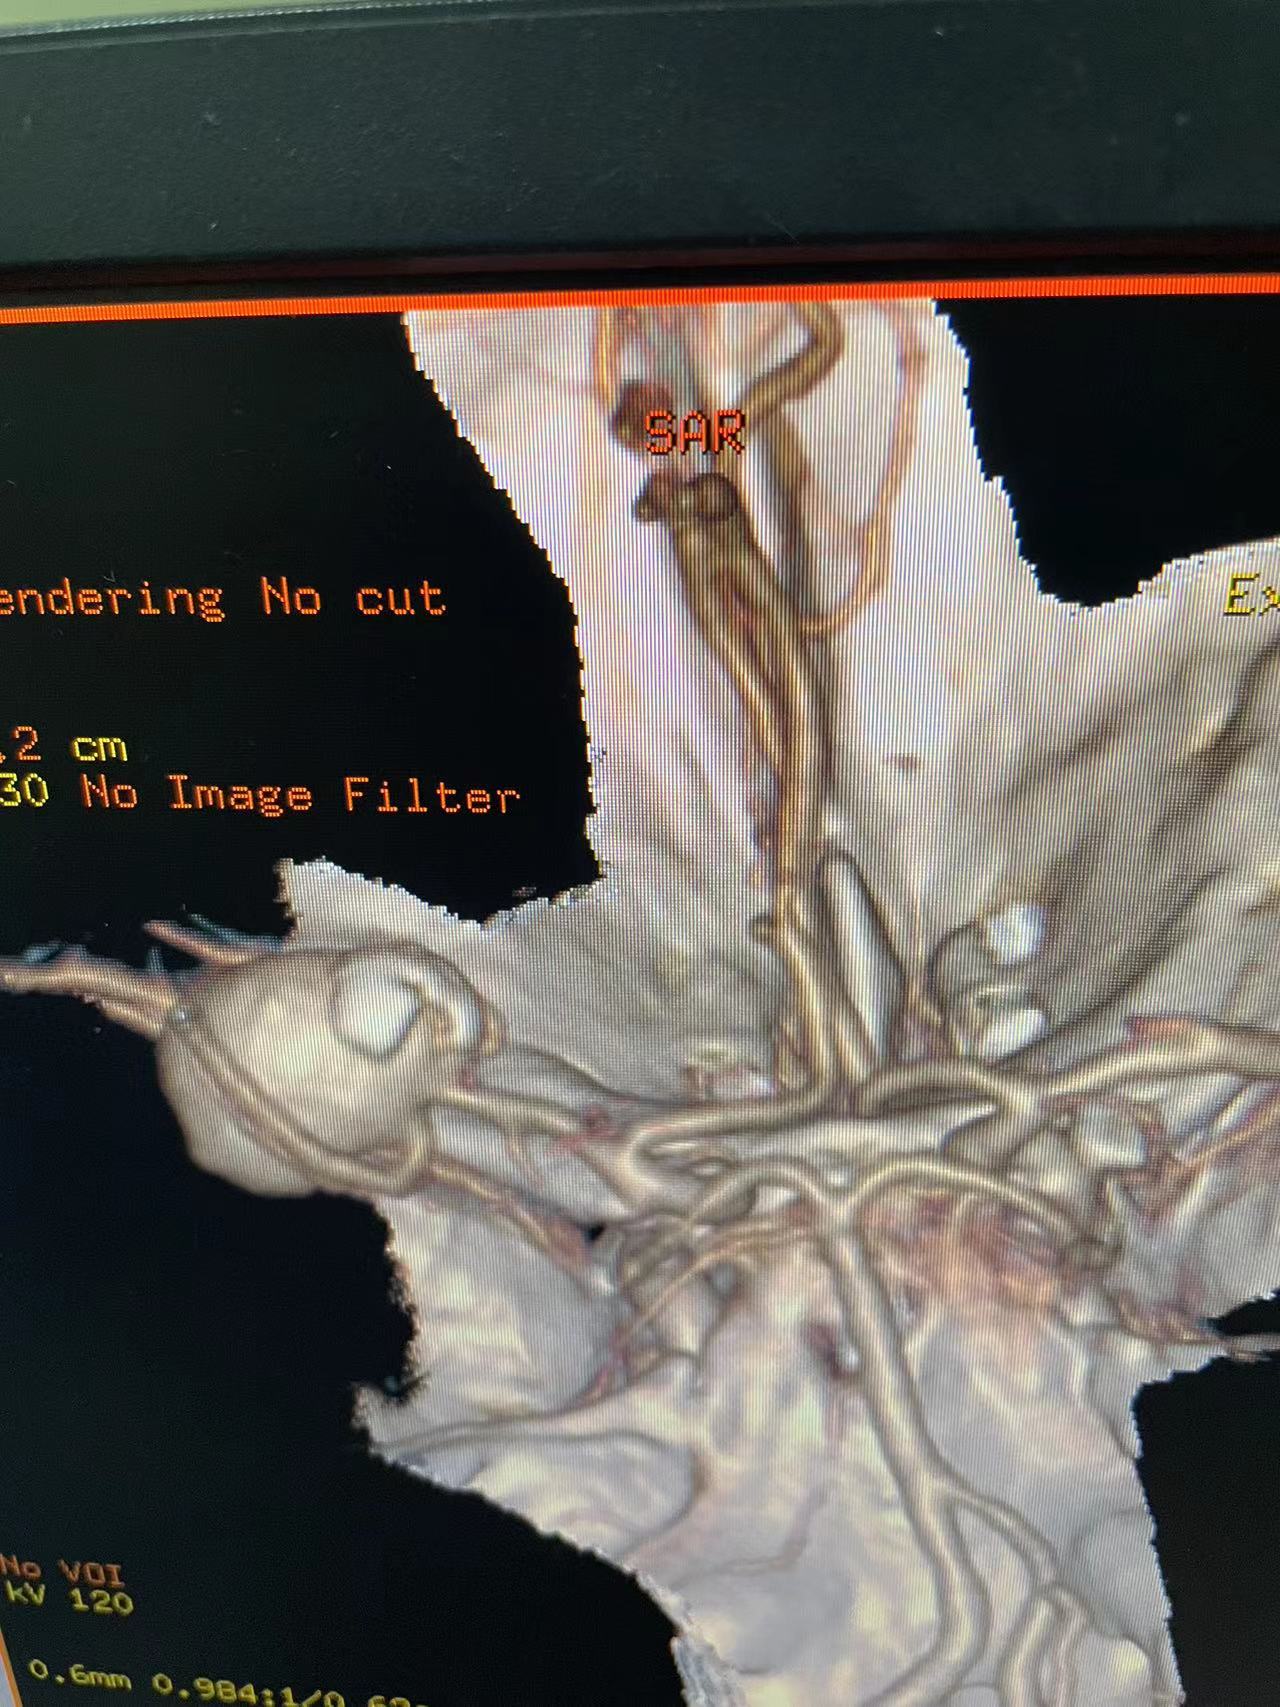

HRQ、女,66岁,463177,因头昏头疼2天,吐词不清1天于20230203日16时24分入院。右侧肢体肌力四级。

指导手术者:成都中医药大学附属医院神经外科主任李定君教授。

既往患者肾上腺嗜铬细胞瘤术后,患者血压波动大!